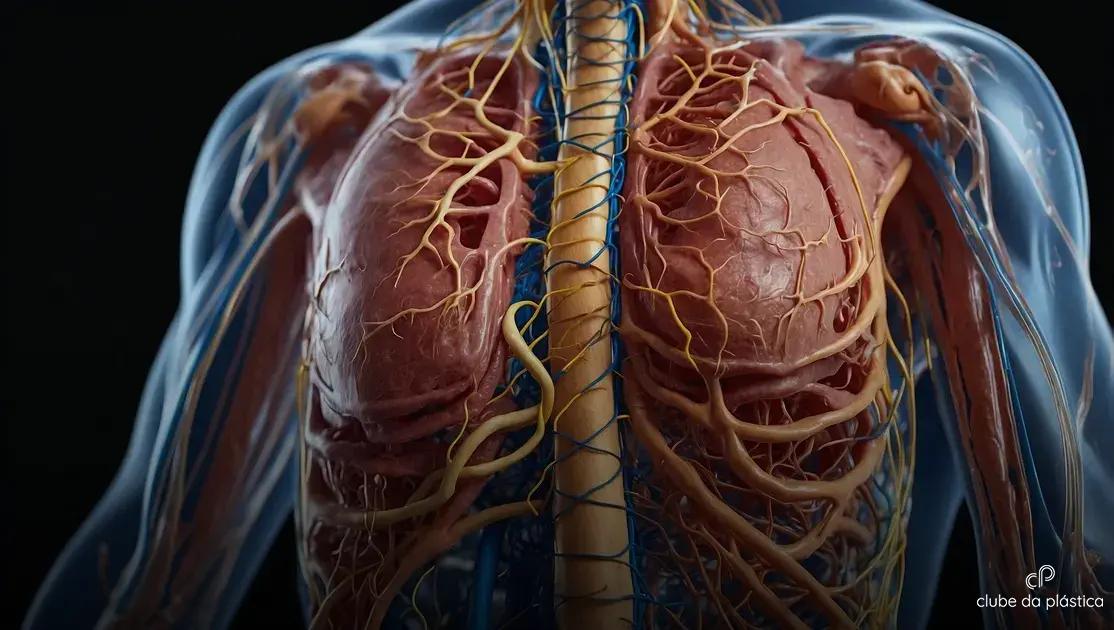

A drenagem linfática é uma técnica de massagem que estimula o sistema linfático do corpo, ajudando a eliminar o excesso de líquidos e toxinas. O sistema linfático funciona como uma rede de vasos e gânglios que transportam a linfa, um líquido transparente rico em proteínas, células do sistema imunológico e resíduos metabólicos. Essa rede é essencial para manter o equilíbrio dos fluidos corporais e para a defesa contra infecções. A drenagem linfática atua ao melhorar o fluxo da linfa, acelerando a remoção desses líquidos acumulados em regiões como pernas, braços e abdômen.

O processo de drenagem é realizado com movimentos suaves, rítmicos e específicos, direcionados para os gânglios linfáticos, que funcionam como filtros naturais. Esses gânglios ficam localizados em áreas estratégicas do corpo, como pescoço, axilas, virilha e atrás dos joelhos, e sua função principal é filtrar e destruir agentes nocivos ao organismo. Ao estimular esses pontos, a massagem ajuda a desbloquear o sistema linfático e a promover a circulação da linfa do tecido para o sistema circulatório, onde será eliminada.

O sistema linfático é composto por vasos que se assemelham às veias, mas que carregam a linfa ao invés de sangue. Seu papel é fundamental na manutenção da imunidade e no equilíbrio hjídricometabólico do corpo. Diferente do sistema circulatório sanguíneo, o sistema linfático não possui uma bomba como o coração, dependendo da movimentação muscular e da pressão externa para impulsionar o fluxo da linfa. Por isso, a drenagem linfática manual complementa esse processo natural, facilitando a circulação da linfa e prevenindo edema.

O sistema linfático é fundamental na eliminação de resíduos e substâncias que o corpo não necessita, incluindo parte da gordura acumulada nos tecidos. Ele funciona como uma rede de drenagem que coleta a linfa — um líquido formado por água, proteínas, células do sistema imunológico e resíduos metabólicos — e a transporta até o sistema circulatório. Quando a gordura localizada é mobilizada, seja por dietas, exercícios ou técnicas como a drenagem linfática, ela é quebrada em moléculas menores, chamadas ácidos graxos, que entram na linfa para serem eliminadas.

Essa gordura fragmentada não desaparece magicamente, mas segue um caminho específico no organismo, especialmente pelo sistema linfático, até chegar à corrente sanguínea. A partir daí, o corpo utiliza essas moléculas como fonte de energia, ou elas são processadas e eliminadas principalmente pelos pulmões, fígado e rins. O sistema linfático, portanto, age como um sistema auxiliar essencial para o transporte e a eliminação eficável dessas partículas gordurosas, prevenindo acúmulos que poderiam causar inchaços ou complicações.

Como a gordura é levada pelo sistema linfático

Ao contrário do sistema venoso, que retorna o sangue ao coração, o sistema linfático coleta o fluido intersticial dos tecidos, incluindo resíduos celulares e gordura quebrada, conduzindo-os pelos vasos linfáticos até os gânglios. Esses gânglios funcionam como filtros biológicos, capturando substâncias indesejadas e facilitando sua decomposição ou eliminação. Durante uma sessão de drenagem linfática, a estimulação manual ativa essa rede, acelerando o transporte desses resíduos, incluindo os lipídios.

Interação com outros sistemas do corpo

O papel do sistema linfático vai além da eliminação de gordura. Ele atua sincronizado com o sistema circulatório e órgãos excretores para manter o equilíbrio do organismo. Por exemplo, as moléculas de gordura transportadas pela linfa são enviadas à corrente sanguínea, onde podem ser usadas como energia, enquanto os órgãos como fígado e rins ajudam a filtrar e excretar os resíduos metabólicos gerados. Essa colaboração entre sistemas é essencial para a saúde e para o efeito esperado da drenagem linfática.